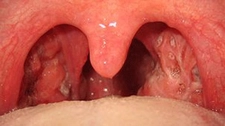

Bademcik İltihabı Nedir?Bademcik iltihabı, bademciklerin (tonsiller) iltihaplanması durumu olarak tanımlanır. Genellikle viral veya bakteriyel enfeksiyonlardan kaynaklanır ve boğazda ağrı, yutkunma güçlüğü ve ateş gibi belirtilerle kendini gösterir. Bademcikler, vücudun bağışıklık sisteminin bir parçası olarak görev yapar ve enfeksiyonlarla savaşmada önemli bir rol oynar. Ancak, aşırı enfeksiyon durumlarında iltihaplanabilirler. Bademcik İltihabının BelirtileriBademcik iltihabı, çeşitli belirtilerle kendini gösterebilir. Bu belirtiler arasında:

Bu belirtiler, bademcik iltihabının ciddiyetine bağlı olarak değişiklik gösterebilir ve bazı durumlarda komplikasyonlara yol açabilir. Bademcik İltihabının NedenleriBademcik iltihabının başlıca nedenleri şunlardır: